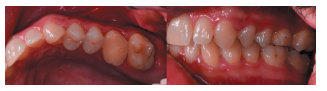

En la Historia Clínica no se evidenciaron antecedentes médico-quirúrgicos de interés, alergias medicamentosas conocidas ni hábitos nocivos. En la exploración extraoral no se apreciaron datos relevantes. En la exploración intraoral se apreciaron dientes no restaurables en posición de 2.6 y 4.6 y la presencia de los terceros molares inferiores retenidos. (Figuras 1 y 2).

Se planificó la exodoncia del 4.6 y 2.6, y el legrado de los procesos apicales, y se le sugirió al paciente el autotrasplante del tercer molar superior izquierdo (2.8) para sustituir el 2.6 (Figura 5).